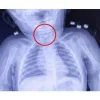

Tekirdağ'da 7 aylık bir bebek, yemek borusuna çengelli iğine kaçması sonucu Tekirdağ Devlet Hastanesine sevk edildi. 7 aylık erkek bebeğin yutup yemek borusuna takılan açık çengelli iğne Tekirdağ Devlet Hastanesi'nde yapılan girişim ile başarıyla alındı. Gastroenterolojik Cerrahi Uzmanı Dr. İhsan Gündüz ile Anestezi Uzmanı Dr. İbrahim Çetin'in yaptığı operasyon sonucu bebek sağlığına kavuştu.

Hastane Başhekimi Aykut Demirkıran, bebeğin sağlık durumunun iyi olduğunu ifade ederek, anne ve babaları, çocuklarının yabancı cisim yutma tehlikesi karşı uyarıda bulundu.